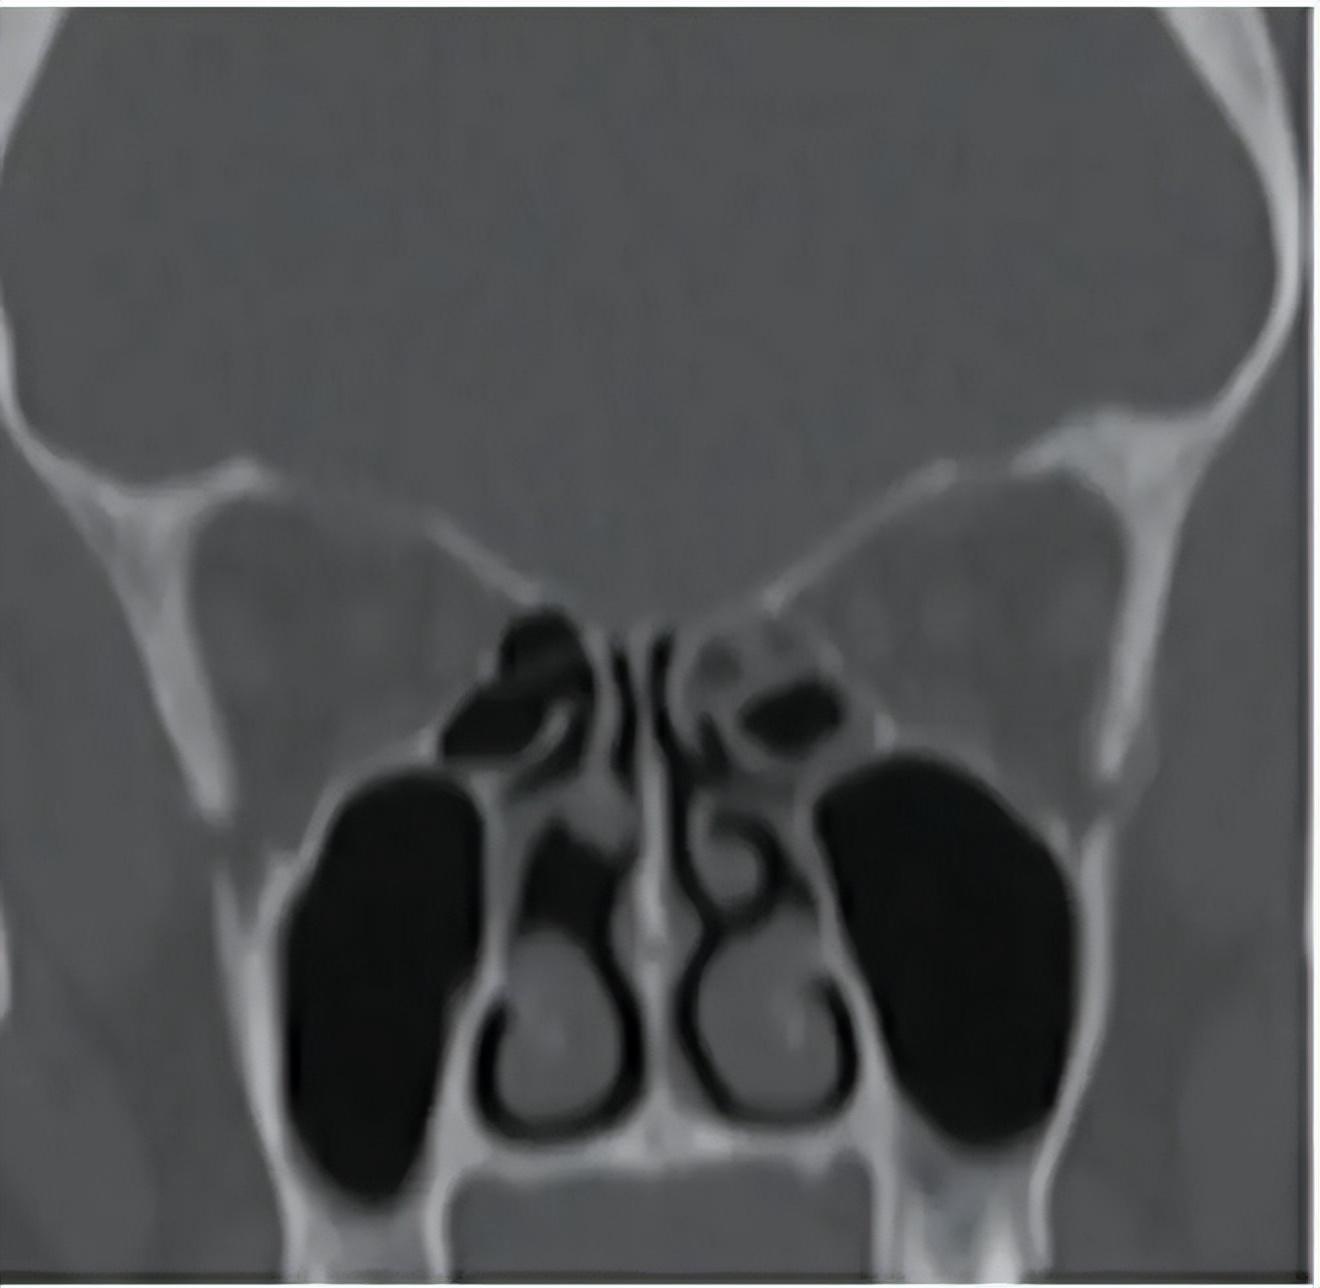

在一項研究[5]中,37 名確診挖鼻癖的患者中,有 32 人出現鼻中隔穿孔,佔 86.5%。這種損傷會導致鼻腔氣流改變,進而出現結痂、鼻塞、鼻出血、面部不適甚至“吹口哨樣”氣流聲等症狀。

一位挖鼻癖患者的鼻竇鼻腔 CT,顯示中鼻甲頭部缺失。圖源:參考文獻[6]